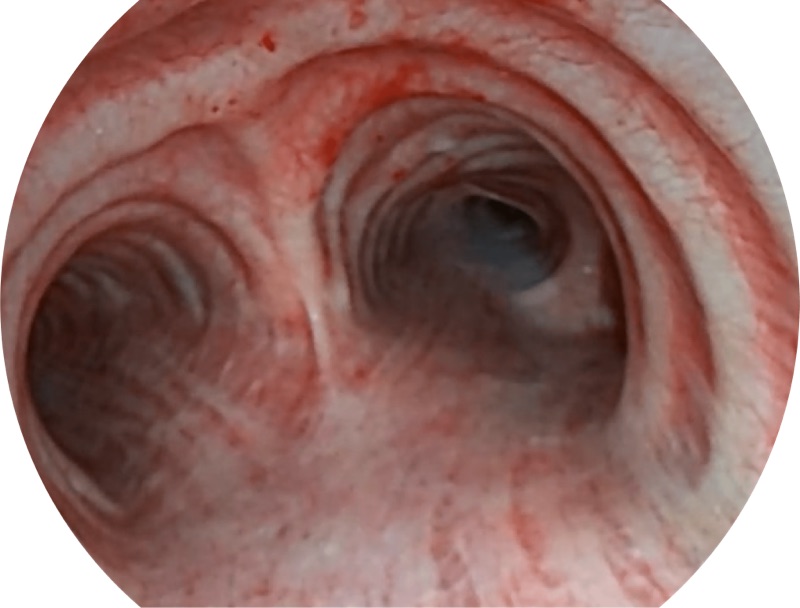

白光